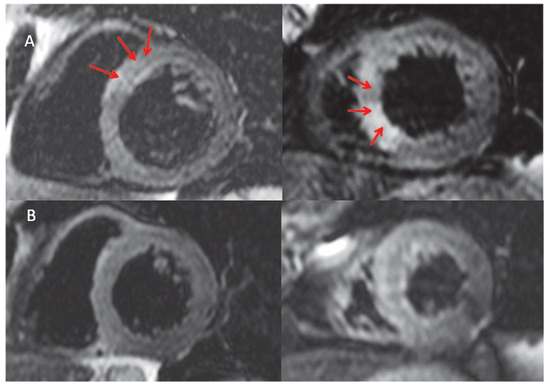

Left Ventricular Apical Ballooning Syndrome with Extensive Myocardial Late Gadolinium Enhancement: Tako-Tsubo Cardiomyopathy, Perhaps Not as Benign as Previously Thought?

by Vincent Gabus, Juerg Schwitter, Eric Eeckhout and Didier Locca

Cardiovasc. Med. 2012, 15(11), 325; https://doi.org/10.4414/cvm.2012.00120 - 21 Nov 2012

Aim: In patients meeting the criteria for LV apical ballooning syndrome, CMR typically identifies myocardial oedema without Late Gadolinium Enhancement (LGE). However, LGE does not exclude LV apical ballooning syndrome and small necrotic areas can be seen in the acute setting resolving at follow-up. Results: We describe the case of a 61 year-old woman admitted with a 2 h history of retrosternal chest pain. ECG demonstrated Q waves and dynamic ST segment elevation. Cardiac enzymes on admission were elevated. Coronary angiography showed unobstructed coronary arteries. Left ventriculography showed apical ballooning. Cardiac Magnetic Resonance (CMR) revealed antero-septal and anterior akinesia. Myocardial oedema was seen in the septal wall. Late gadolinium enhancement (LGE) was seen in the same territory indicating the presence of necrosis. A follow up CMR scan was performed at 3 months showing a complete resolution of the septal oedema. However, on LGE sequences there was evidence of persistent extensive fibrotic scar located in the septal wall. The size of this fibrotic scar was 20% bigger than on the previous scan. Conclusions: Detection and quantification of a scar is important, as scar tissue on LGE images has been described as a predictor of major adverse cardiac events. Therefore, this case suggests that the spectrum of Tako-tsubo cardiomyopathy may include a more severe variant than previously described. CMR examinations could serve as a useful means to identify severe cases and predict potential complications of this pathology as well as to drive therapeutic decisions. Full article

Figure 1